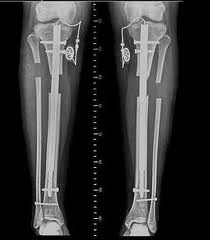

So, salahkah ingin bertubuh tinggi? tentu saja tidak, tetapi terlalu terobsesi menjadikan segalanya tidak lebih baik. Pernah dengar tentang tulang yang dipatahkan lalu disambung biar lebih tinggi? Atau minum hormon pertumbuhan sehingga tulangnya besar-besar dan aneh? Saya rasa-rasa memang terlalu berlebihan. Padahal tubuh ideal sehat proposional fungsional (lagi bercermin-red) adalah yang lebih bernilai kan? Oh ya kalau masih usia pubertas sebaiknya pakai cara alami saja dah (klik disini).